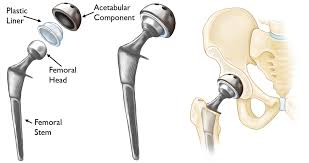

— Our Services

— Our Product

Take a Look at Our Awesome Gallery